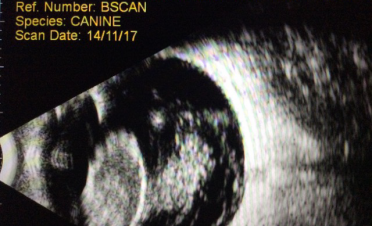

Ecografía bidimensional

Permite visualizar imágenes del globo ocular y la órbita en dos dimensiones.

Se suele utilizar en casos de:

- desprendimiento de retina

- hemorragias en vítreo

- cataratas

- hiperplasias

- medición de lentes intraoculares